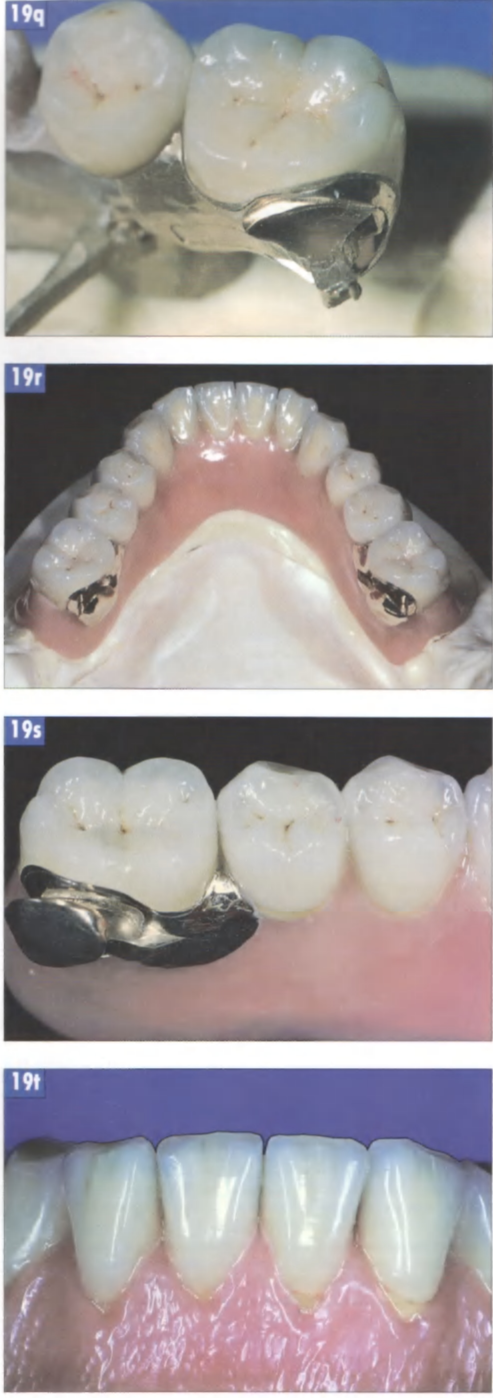

Рис. 19р. Моделирование искусственных зубов поверх корпуса замка осуществляется только после изготовления вторичной детали.

Рис. 19q. Изготовление искусственных керамических зубов требует от зубного техника точного представления о форме и практического опыта послойной облицовки. После изготовления керамические зубы наклеиваются на вторичный каркас. Чтобы предотвратить окисление задвижки при изготовлении открывающей головки, перед моделированием ее нужно покрыть флюсом.

Рис. 19r.

Готовая реставрация с соединительным элементов типа балка-замок: вид со стороны поверхности окклюзии.

Рис. 19s.

Задвижной замок в открытом состоянии.

Рис. 19t.

Готовый протез нижней челюсти: вид спереди.